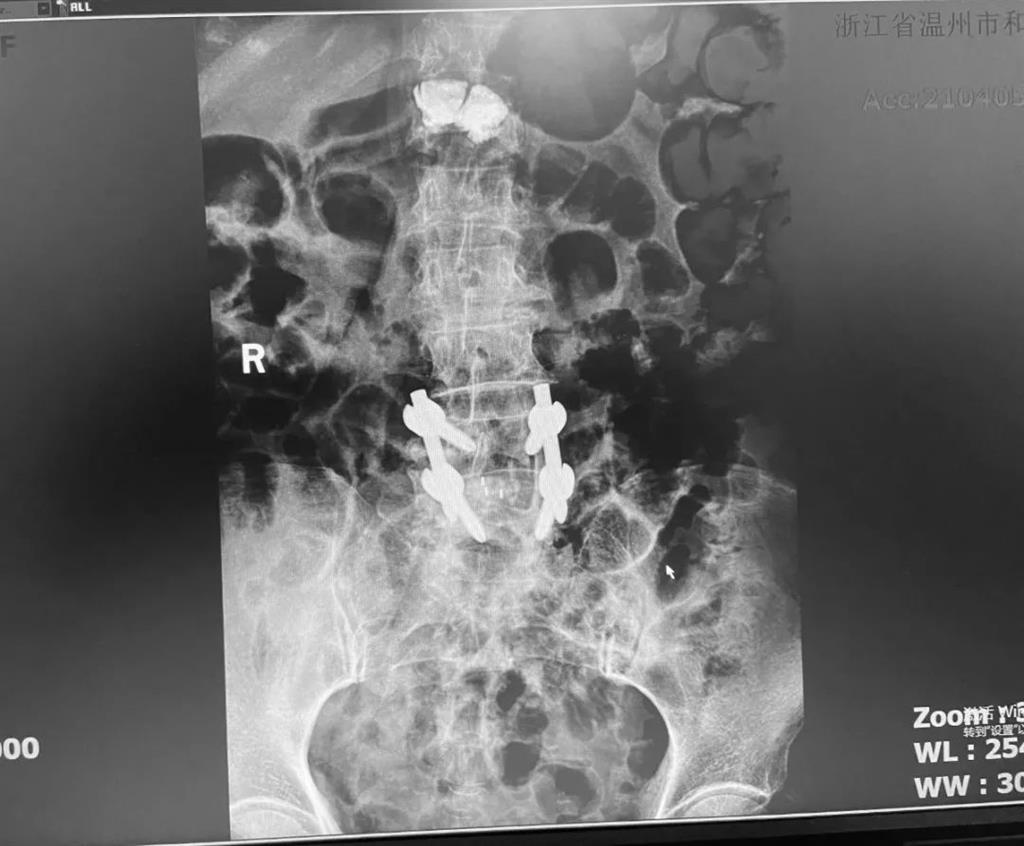

據(jù)了解,脊柱內(nèi)鏡下腰椎融合術(shù)只需要打幾個(gè)“鑰匙孔”即可完成。聽(tīng)起來(lái)是不是很簡(jiǎn)單?在脊柱內(nèi)鏡下,劉丹主任先后為患者進(jìn)行了椎管減壓、椎間盤摘除,再實(shí)施椎弓根螺釘放置、椎體植骨融合內(nèi)固定,一系列步驟有條不紊。

看似簡(jiǎn)單的幾個(gè)步驟,但實(shí)際上很復(fù)雜,需要主刀醫(yī)生有豐富的手術(shù)經(jīng)驗(yàn)和細(xì)致耐心的操作。

術(shù)中只需切開(kāi)4個(gè)如“鑰匙孔”般大小的孔道